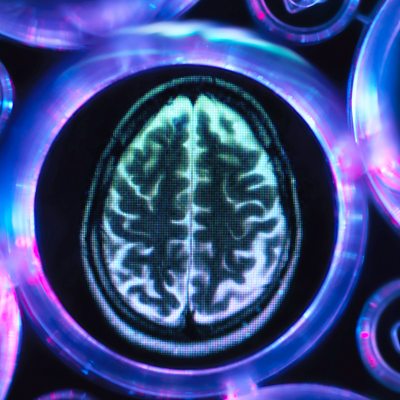

Image of a Troubled Mind

Dr Mark Lythgoe investigates the technology of brain scanning. Will this technique ever help people suffering from mental illnesses such as depression and schizophrenia?